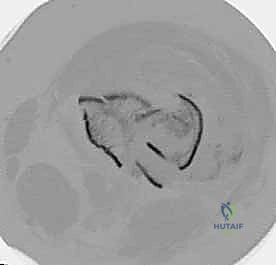

- الأشعة المقطعية (CT Scan): وهي ضرورية جداً في كسور عظم الفخذ البعيدة، خاصة إذا كان الكسر يمتد إلى داخل مفصل الركبة (Intra-articular fractures). تساعد الأشعة المقطعية الدكتور هطيف على بناء نموذج ثلاثي الأبعاد للكسر، مما يسهل التخطيط الجراحي وتحديد أماكن وضع المسامير بدقة.